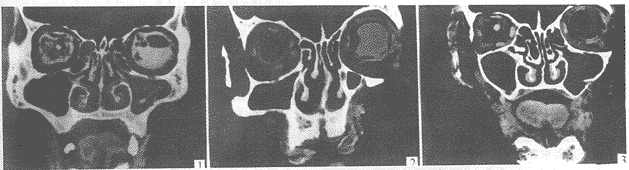

【摘要】目的:为临床开展前颅底外科提供嗅凹必要的影像解剖学资料。方法:取50具成人头颅标本,行鼻窦冠状位薄层CT扫描,重点观测筛顶与筛板的移行情况。结果:观测到筛顶与筛板的移行形式有二种类型:一种是直接斜向筛板;一种是先形成一平台段,在近筛板时徒然下降,形成嗅凹。本组资料中筛顶板与筛板平移的占46%;而形成嗅凹的占54%。在形成嗅凹的资料中,前筛顶板与筛板之间形成的高度差的平均值为8.8mm,后筛顶板筛板之间形成的高度差的平均值为2.8mm,前后嗅凹深度之间经t检验相差非常显著(P<0.01)。结论:了解嗅凹的形成对减少前颅底外科手术及内窥镜鼻窦手术并发症的发生具有十分重要的意义。